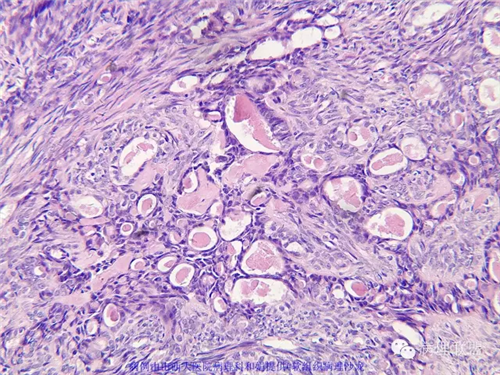

M,57岁,右膝关节外侧皮下肿物10余年,活动度好。

免疫组化结果阴性:S-100,SMA,Calponin,CD10,CD99,CD34,CEA,PHH3。

本例形态学上是非常典型的双相型滑膜肉瘤,滑膜肉瘤临床上大部分表现为生长缓慢的肿瘤。以青壮年多见,主要发生于四肢大关节附近,也可见于其他少见部位,如肺、肾等实质器官,形态学分为5种类型:单相纤维型、单相上皮型、双相型、低分化梭形细胞型和小细胞型。有文献报道个别患者有长达20年的病史。